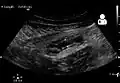

Ultrasound

Abdominal ultrasonography, preferably with doppler sonography, is useful to detect appendicitis, especially in children. Ultrasound can show the free fluid collection in the right iliac fossa, along with a visible appendix with increased blood flow when using color Doppler, and noncompressibility of the appendix, as it is essentially a walled-off abscess. Other secondary sonographic signs of acute appendicitis include the presence of echogenic mesenteric fat surrounding the appendix and the acoustic shadowing of an appendicolith.[59] In some cases (approximately 5%),[60] ultrasonography of the iliac fossa does not reveal any abnormalities despite the presence of appendicitis. This false-negative finding is especially true of early appendicitis before the appendix has become significantly distended. Also, false-negative findings are more common in adults where larger amounts of fat and bowel gas make visualizing the appendix technically difficult. Despite these limitations, sonographic imaging with experienced hands can often distinguish between appendicitis and other diseases with similar symptoms. Some of these conditions include inflammation of lymph nodes near the appendix or pain originating from other pelvic organs such as the ovaries or Fallopian tubes. Ultrasounds may be either done by the radiology department or by the emergency physician.[61]

-

Ultrasound showing appendicitis and an appendicolith.[62]

Ultrasound showing appendicitis and an appendicolith.[62] -

Ultrasound of a normal appendix for comparison. -

A normal appendix without and with compression. Absence of compressibility indicates appendicitis.[59]